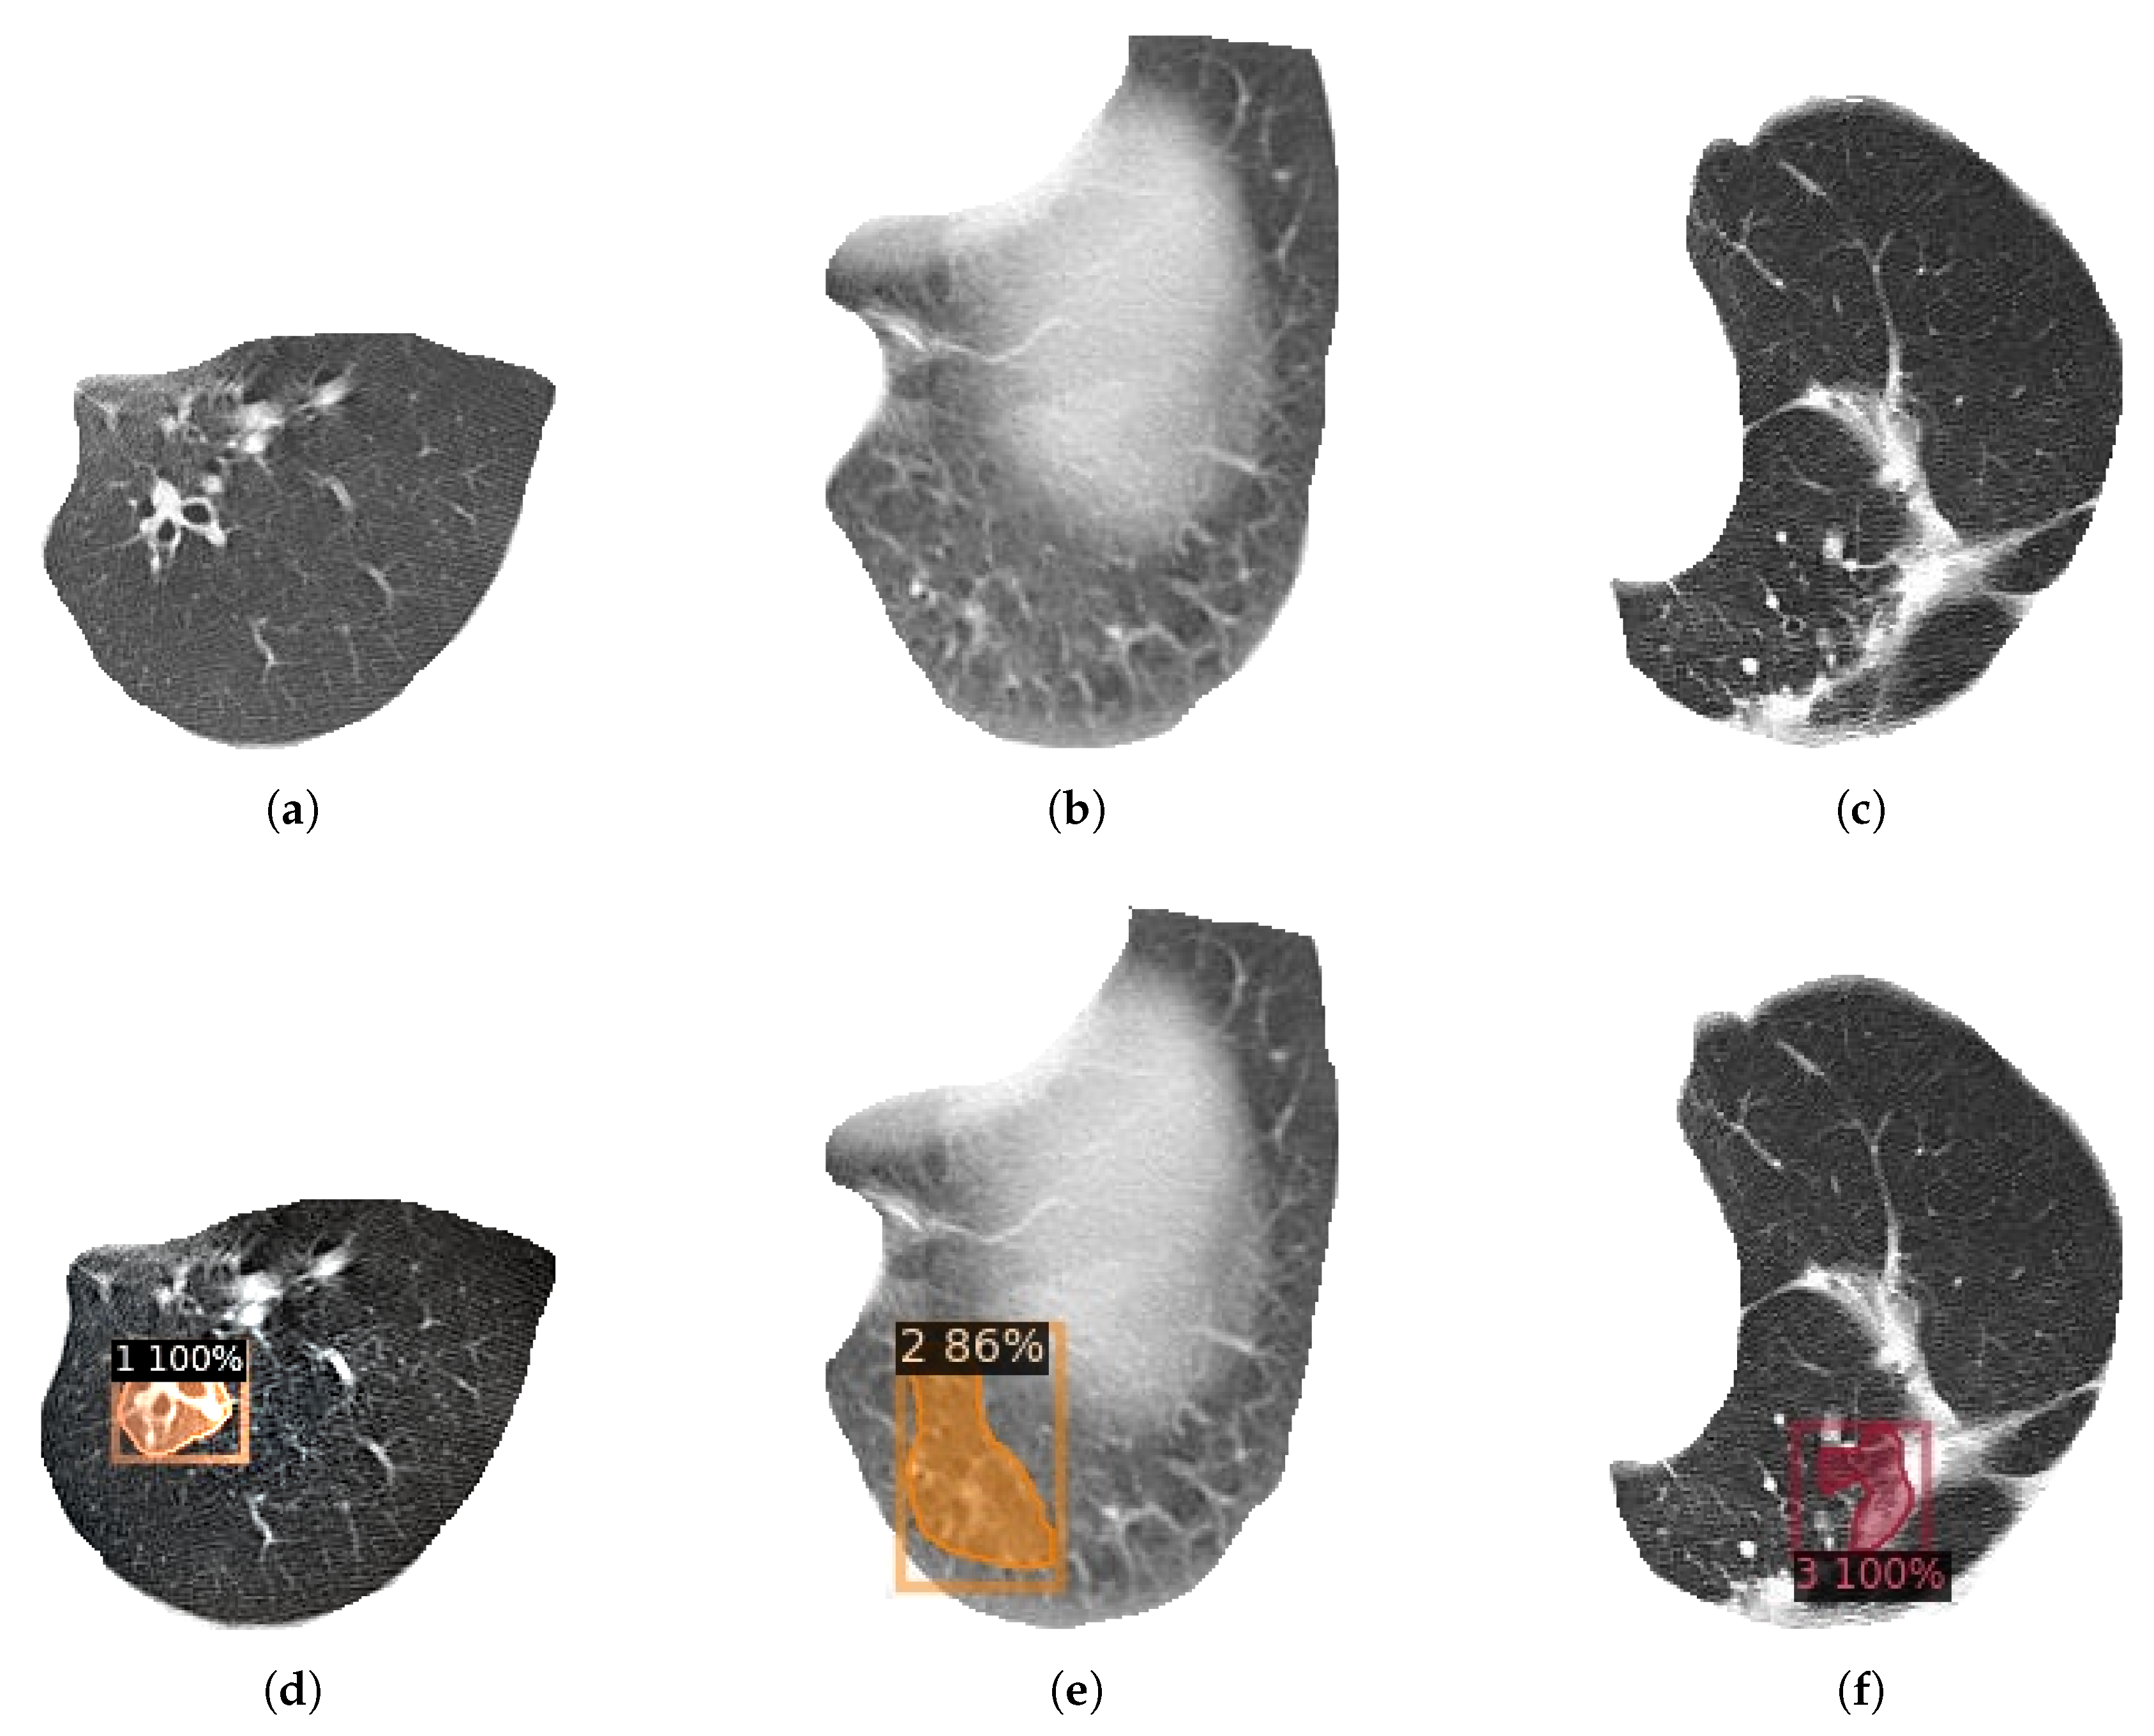

When one or more of the following three criteria were met and tractive bronchiectasis was excluded, the diagnosis of bronchiectasis could be established: 1. The inner diameter of the airway was larger than that of the accompanying pulmonary artery; 2. Distal airway diameter greater than 2 cm from bronchial bifurcation ≥ proximal airway diameter; 3. Bronchi can be seen in lung tissue within 1 cm of costal pleura or mediastinal pleura. If one or more of the radiographers consider that the image does not conform to the diagnosis of bronchiectasis during the image review, they will be reviewed by an associate chief physician specializing in respiratory imaging and make the final diagnosis. The severity of bronchiectasis was divided into three severity grades and rated as 1, 2, and 3. Grade 1 was classified as mild (lumen diameter was 1–2 times of adjacent vessel diameter), 2 was classified as moderate (lumen diameter was 2–3 times of adjacent vessel diameter), and 3 was classified as severe (lumen diameter was more than 3 times of adjacent vessel diameter).

In this study, LDCT images of 120 patients were screened from the above data according to the physical examination results of each center and labeled by doctors according to the above methods and standards. A total of 1992 patients with bronchiectasis were labeled, including 588 patients with category 1, 566 patients with category 2, and 838 patients with category 3. The subdivision for each class is reported in Table 3, and examples of bronchiectasis images with different labeled categories are shown in Figure 1.

Figure 1. Images of bronchiectasis of different labeled class.